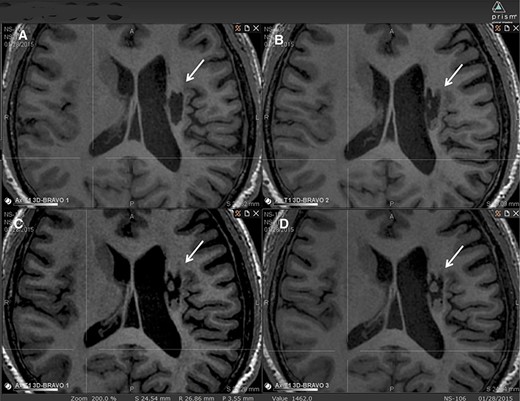

圖2:腔內(nèi)組織生長(zhǎng)的縱向MRI示例。

圖中顯示了B組 (#106) 受試者在T1MRI上隨時(shí)間的變化。

(A):基線時(shí),(B) 6個(gè)月隨訪時(shí),(C) 12個(gè)月隨訪時(shí),(D) 24個(gè)月隨訪時(shí)。箭頭表示梗塞腔。

可以看到兩個(gè)組織團(tuán)塊,在基線時(shí)不存在,推測(cè)是來(lái)自植入的NSI-566,隨著時(shí)間的推移,它們似乎慢慢填滿了腔體。